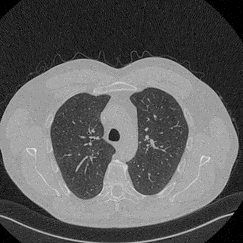

In this work, we present Eformer - Edge enhancement based transformer, a novel architecture that builds an encoder-decoder network using transformer blocks for medical image denoising. Non-overlapping window-based self-attention is used in the transformer block that reduces computational requirements. This work further incorporates learnable Sobel-Feldman operators to enhance edges in the image and propose an effective way to concatenate them in the intermediate layers of our architecture. The experimental analysis is conducted by comparing deterministic learning and residual learning for the task of medical image denoising. To defend the effectiveness of our approach, our model is evaluated on the AAPM-Mayo Clinic Low-Dose CT Grand Challenge Dataset and achieves state-of-the-art performance, $i.e.$, 43.487 PSNR, 0.0067 RMSE, and 0.9861 SSIM. We believe that our work will encourage more research in transformer-based architectures for medical image denoising using residual learning.